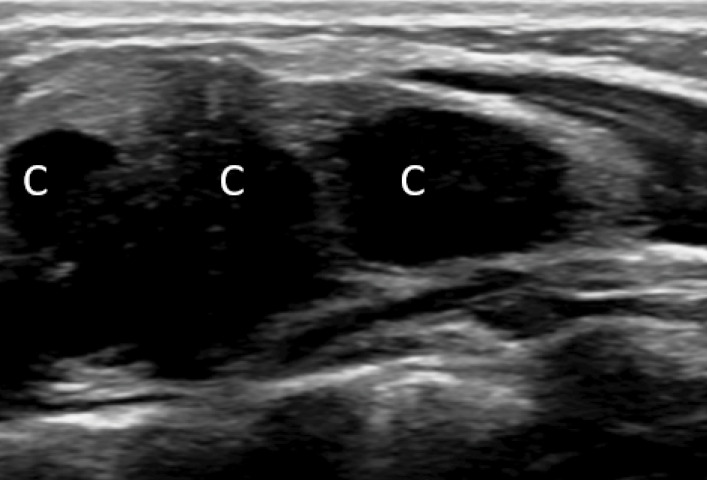

教学点:在血液结果正常且胸骨肿胀迅速增长且无创伤和全身性炎症疾病的婴儿中建立对儿童期自限性胸骨肿瘤(SELSTOC)的认识。

Teaching point: Creating awareness of self‑limiting sternal tumour of childhood (SELSTOC) in infants with rapidly growing sternal swelling with normal blood results and without trauma and systemic inflammatory diseases.